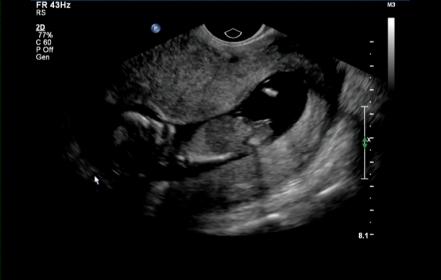

Thank you all you beautiful ladies who helped get me through the 7 week wait between scans!! Now for the long wait till she arrives :) I just cant wait to meet her!

Attachment 7660